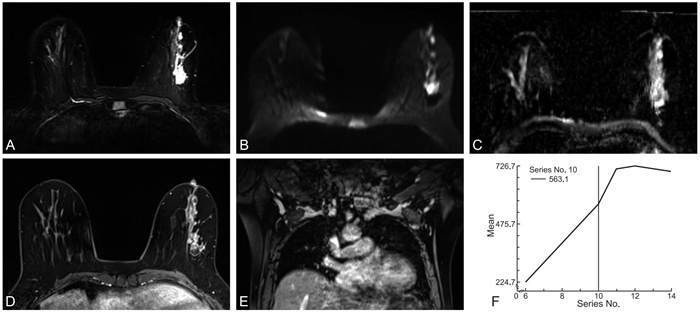

Correlation between MRI imaging characteristics of non-mass-like breast cancer and Ki-67 expression levels in non-mass breast cancer

XU Ling, ZHAO Hong, GONG Xijun, ZOU Liwei, WANG Longsheng

2025, 23(11): 1915-1919. doi: 10.16766/j.cnki.issn.1674-4152.004259

1632 1

Abstract:

Objective  To investigate the correlation between MRI features of non-mass breast cancer and Ki-67 expression, providing a basis for non-invasive preoperative assessment of tumor proliferative activity.  Methods  From January 2020 to December 2023, fifty-one patients with pathologically confirmed non-mass breast cancer were enrolled at the Second Affiliated Hospital of Anhui Medical University. Based on postoperative pathology, they were stratified into a low Ki-67 expression group (n=15) and a high-expression group (n=36). Comparisons included clinical data and MRI features [mean apparent diffusion coefficient (ADC) value, axillary lymph node metastasis, enhancement distribution, internal enhancement pattern, time-intensity curve (TIC) curve].  Results  No significant differences were observed in age, mean ADC value, enhancement distribution, or internal enhancement between groups (P>0.05), with clustered ring enhancement predominating (47.06%, 24/51). The high-expression group showed significantly higher axillary lymph node metastasis rates than the low-expression group [58.33%(21/36) vs. 26.67% (4/15), P=0.041].TIC curves in the high Ki-67 group were categorized as type Ⅰ (1 case), type Ⅱ(15 cases), and type Ⅲ (20 cases), while the low Ki-67 group showed type Ⅰ (3 cases), type Ⅱ (9 cases), and type Ⅲ (3 cases). TIC distribution differed significantly between groups (P=0.018), with statistically significant differences in Ki-67 expression between type Ⅰ and Ⅲ curves (Bonferroni-corrected, P < 0.017). Axillary lymph node metastasis rate positively correlated with Ki-67 expression (Kendall' s tau-b=0.289, P=0.041). mean ADC value negatively correlated (r=-0.334, P=0.017), and TIC curve type positively correlated (r=0.303, P=0.031). The combined AUC of axillary lymph node metastasis and TIC curves for predicting Ki-67 expression was 0.761 (sensitivity 0.861, specificity 0.667), outperforming individual indicators (AUC: 0.658, 0.678).  Conclusion  Non-mass breast cancer frequently exhibits clustered ring enhancement. Axillary lymph node metastasis and TIC curves correlate with Ki-67 expression, and their combination improves predictive efficacy, offering value for preoperative assessment of tumor proliferative activity.